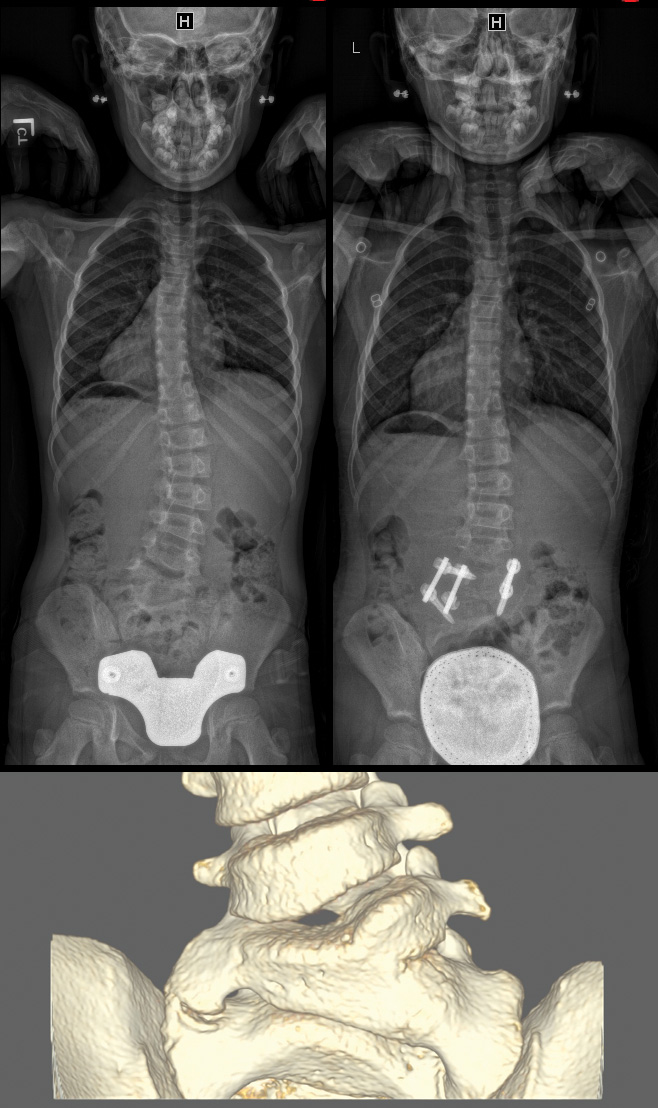

Clinical and radiographic image of a controlled growing Magnetic Growth Rods These growing rods use a magnetic remote. A system of external magnetic distraction of implanted spinal rods was first. The magec system utilizes innovative magnetic technology within adjustable growing rods and an external remote controller (erc) to help avoid distraction. Magec growing rods are a new surgical treatment for children with severe spinal deformities that uses implantable rods and an. Magnetic Growth Rods.